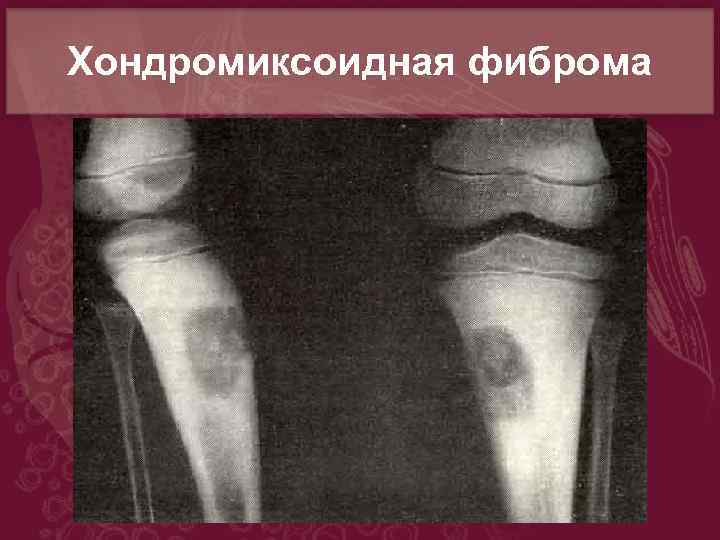

Рентгеновские снимки доброкачественных опухолей костей